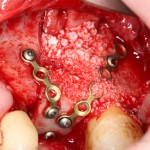

Итого, наиболее оптимальным в данной ситуации оказалась направленная тканевая регенерация с использованием барьерных мембран. В качестве барьерной мембраны у нас будет Geistlich BioGide. Ее очень легко адаптировать и позиционировать:

А в качестве трансплантата — аутокостная стружка, которую я насобирал заранее из области угла нижней челюсти:

Начну с того, что BioGide — это лучшее, что есть сейчас на рынке, а остальные мембраны ей завидуют. Как и в случае с макродизайном имплантов, именно физические свойства определяют как удобство использования, так и возможность достижения нужного результата. Прочность, эластичность, легкая адаптация и адгезия делают ненужными использование фиксирующих пинов. Мы просто закрываем мембраной графт — и все, можно накладывать швы:

В другом ракурсе видно, какой объем тканей мы восстанавливаем: